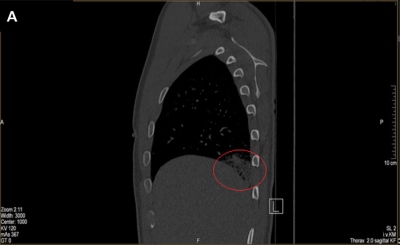

Komplikace nastala v sedmém měsíci při terapii Eliquis tbl. 2× 2,5 mg (snížená dávka po šesti měsících terapie dle SPC): recidiva HŽT ve formě ileofemorální HŽT LDK současně s bilaterální hemodynamicky stabilní plicní embolizací (provedeno CTAG) (obr. 2). Laboratorně hodnota D-dimerů 885 µg/l [1..190], hodnota FVIII 174 IU/ml [norma do 150], provedený základní onkologický screening byl v normě, byly vyloučeny „vzácné“ formy trombofilie (F:VII, IX, XI, XII, JAK-2 neg.).